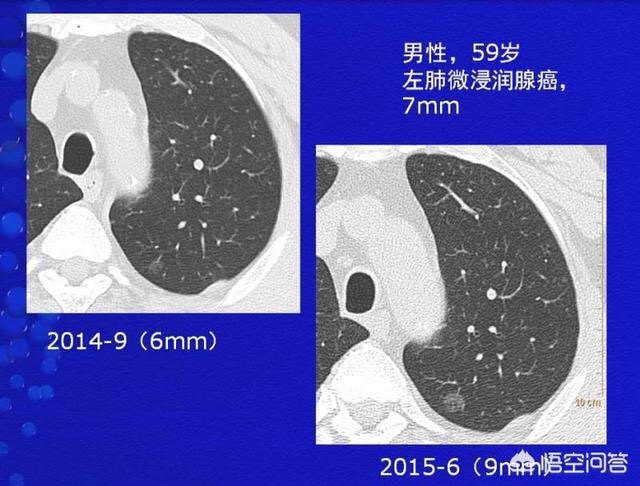

比如这位59岁的男性病人,体检发现左侧6毫米肺结节,呈纯磨玻璃密度。这种形态的结节,良恶性都可以见到,良性的在随访中会吸收。这位病人经过9个月的随访观察,结节增大了3毫米,手术切除证实为微浸润肺腺癌。

一般来说,一年内增大超过2毫米的磨玻璃结节,分期就属于微浸润腺癌以上,需要积极处理。